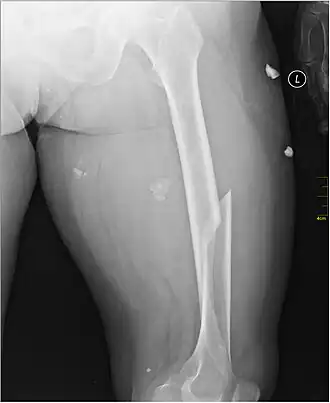

| X-ray image of a femoral shaft fracture | |

A femoral fracture is a bone fracture that involves the femur. They are typically sustained in high-impact trauma, such as car crashes, due to the large amount of force needed to break the bone. Fractures of the diaphysis, or middle of the femur, are managed differently from those at the head, neck, and trochanter; those are conventionally called hip fractures (because they involve the hip joint region). Thus, mentions of femoral fracture in medicine usually refer implicitly to femoral fractures at the shaft or distally.

Anterior-posterior (AP) and lateral radiographs are typically obtained.[4] In order to rule out other injuries, hip, pelvis, and knee radiographs are also obtained.[5] The hip radiograph is of particular importance, because femoral neck fractures can lead to osteonecrosis of the femoral head.[4]